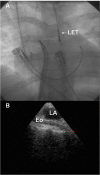

Catheter ablation of atrial ablation (AF) has become an important therapy in recent years. As with all evolving techniques, unexpected complication may occur. Atrioesophageal fistula is a very rare complication of AF catheter ablation. Described for the first time in two very experienced centers in 2004, this complication is the most dreadful and lethal among all the others related to AF catheter ablation. Its clinical presentation is extremely variable. Rapid diagnosis and surgical therapy may prevent death. This review article will summarize the risk factors, diagnosis, treatment and possible preventive strategies for this condition.